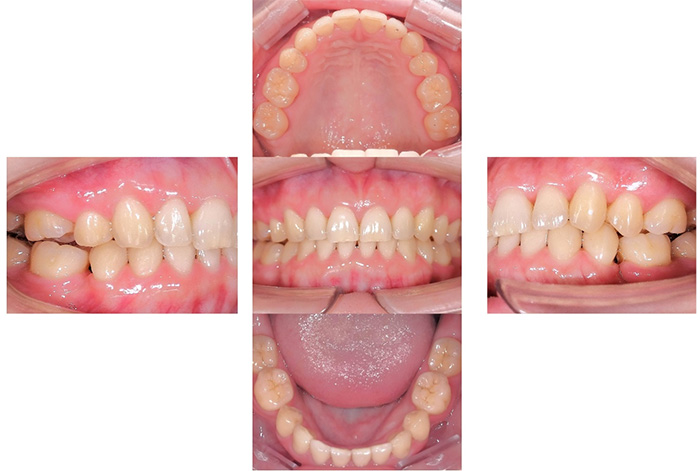

Before

After

今回の患者様は、ディープバイト(過蓋咬合)による前歯の見た目と噛み合わせを気にされて来院されました。ディープバイトとは、上の前歯が下の前歯に深く重なっている噛み合わせのことで、見た目の問題だけでなく、前歯や顎への負担につながることがあります。

本症例では、マウスピース型矯正装置(インビザライン)を用いて治療を行いました。合計84枚のアライナーを使用し、歯並びだけでなく咬合の深さにも配慮しながら治療を進めました。

治療後は、前歯の見た目のバランスが整い、噛み合わせも改善しました。